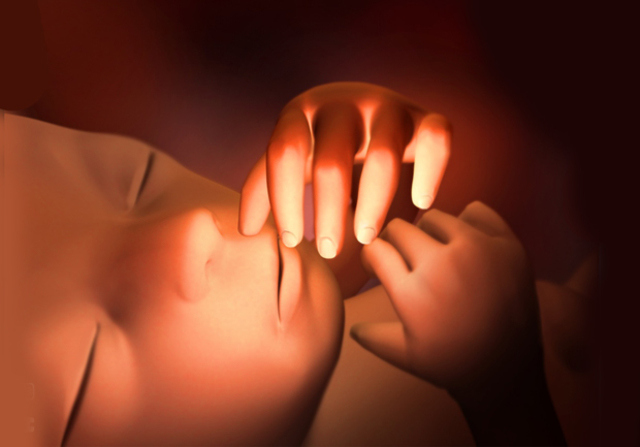

Aparecen las manos con los dedos.

Las piernas se alargan, aparecen los pies con sus dedos correspondientes.

El embrión cada vez tiene más forma humana y se distingue los brazos y los antebrazos, así como las manos que se abren y se cierran y están a la altura de la boca.